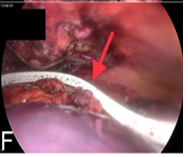

Congenital diaphragmatic hernia (CDH) is a birth defect involving improper formation of the diaphragm, leading to the protrusion of abdominal organs into the chest cavity. The CDH is classified depending on the location of the defect as postero-lateral, central and anterior. Depending on the side, it is classified as right, left and bilateral. A majority of CDH defects are postero-lateral defects and are commonly referred to as Bochdalek hernias (BH). Herein, the authors present the case of a 29 years old male patient diagnosed with a large left recurrent Bochdalek hernia. He was operated for it in another hospital by another surgeon 5 months back. That previous surgical intervention was initially planned via laparoscopy. But, intraoperatively, it had to be converted to open surgery due to technical difficulty. Post the first surgery, after about 1.5 months, he started developing pain in the back of his left chest. However, due to financial constraints, he did not seek any consultation with anyone at that time. The authors successfully performed a laparoscopic repair of this difficult condition. The rationale for reporting this case is to underscore the relative ease of a laparoscopic over open surgical intervention, on the ‘roof’ of the abdomen and also the lower chest. Also, it hopes to highlight that laparoscopic repair of BH is feasible even in challenging, difficult and recurrent scenarios, in an advanced setup backed up by the requisite surgical expertise.